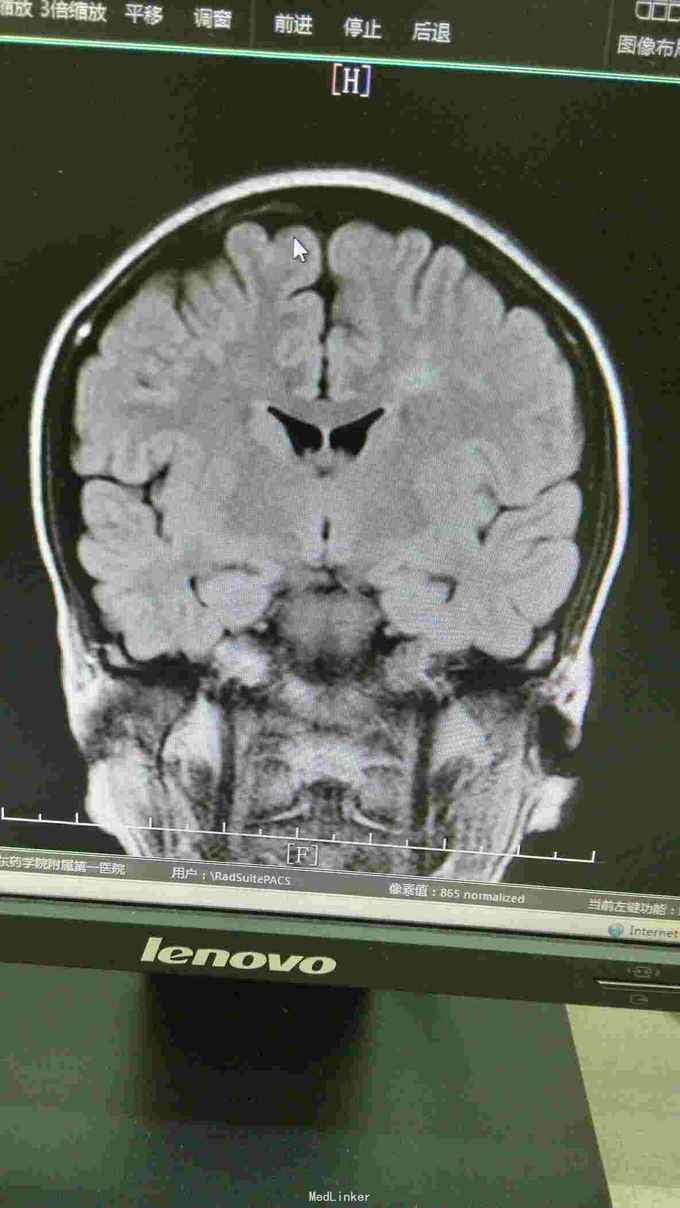

查体:T37.0℃,P110次/分,R26次/分,BP96/68mmHg。发育正常,营养一般,神志清楚,对答切题,轮椅送入院,查体合作。全身皮肤粘膜无黄染、皮疹,出血点及淤斑,未见Janeway结节,未见Osler结节及甲床下出血,无发绀,未见杵状指、趾,周围血管征阴性。浅表淋巴结未及肿大。巩膜无黄染,结膜无出血。口腔黏膜光滑,咽不红,扁桃体部大,颈静脉无明显搏动,未见怒张,气管居中,胸背部听诊双下肺闻及细小湿啰音。心前区无隆起或抬举性搏动,心尖搏动以左侧第六肋间锁骨中线外1.5cm处明显,未扪及震颤,心界向两侧稍扩大,心率110次/分,律齐,心音有力,P2稍亢进,无固定分裂,心尖区闻及3-4/6级收缩期吹风样杂音,向心底部传导,未闻及舒张期杂音,未闻及心包摩擦音。腹平软,无压痛及反跳痛,肝脾肋下未及,肠鸣音正常。脊柱、四肢关节无异常,活动好,双下肢无浮肿。 2015年10月30日汕头市中心医院心彩超:二尖瓣及瓣下腱索及左室心内膜多发赘生物形成,二尖瓣前瓣穿孔,重度二尖瓣关闭不全,左心系统扩大,心肌舒张功能下降,收缩功能正常,感染性细菌性心内膜炎,微量心包积液。 2015-11-1血常规:中性粒细胞比例 0.949,血红蛋白浓度 117.000(g/L),中性粒细胞计数 18.360(10E9/L),白细胞计数 19.350(10E9/L),血小板计数 343.000(10E9/L),红细胞计数 4.350(10E12/L)。 B超:双侧颈动脉血流通畅,双侧椎动脉未见狭窄。双侧甲状腺不大、未见占位,血供尚丰富。双侧颈部淋巴结声像,双侧乳腺未见明显占位,超声BI-RADS分类1类,双侧腋窝淋巴结声像。双肾未见结石与积水,双肾动脉主干血流连续,膀胱未见明显结石,双侧肾上腺区未见明显占位。肝脾胰不大,未见占位,胆囊未见明显结石,子宫及双侧附件区未见明显占位,宫后积液(少量)。 胸部CT:1、两下肺叶后基底段局部节段性肺炎。右肺中叶少许纤维化病灶。2、双侧胸腔少量积液。 胸片:考虑双肺炎症。 心电图:心率84次/分,窦性心律,肢体导联低电压,前间壁R波上升不良。 心彩超:1、考虑感染性心内膜炎:二尖瓣赘生物形成,伴中重度二尖瓣反流。中度三尖瓣反流。3、左房内径增大,肺动脉增宽。 头颅MR:左侧额叶、左侧放射冠侧脑室前角旁脑白质异常信号,考虑感染性病变及缺血灶可能性大。 2015-11-2查血常规:中性粒细胞比例 0.840,血红蛋白浓度 103.000(g/L),中性粒细胞计数 14.730(10E9/L),白细胞计数 17.540(10E9/L),红细胞计数 3.890(10E12/L),血小板计数 353.000(10E9/L)。 10月31日左上肢、右上肢、下肢血培养均提示:草绿色链球菌,对万古霉素敏感。 2015-11-6肾功能:肌酐 130.000(umol/L),尿素氮 5.250(mmol/L),二氧化碳结合力 30.500(mmol/L),电解质:钠 138.000(mmol/L),氯 96.000(mmol/L),钾 3.500(mmol/L),钙 2.310(mmol/L),肝功能:白、球蛋白比例 1.300,未结合胆红素 10.500(umol/L),总胆红素 17.900(umol/L),丙氨酸氨基转移酶 31.000(U/L),总蛋白 75.000(g/L),球蛋白 32.000(g/L),白蛋白 43.000(g/L),结合胆红素 7.400(umol/L),门冬氨酸氨基转移酶 31.000(U/L),脑钠肽:191.400(pg/ml)。 24小时心电图:窦性心律,房性早搏,部分成对,短阵房速,多源室早,部分成对,部分呈三联律,短阵室速。

关于感染性心内膜炎此前我发布过一个病例,但不同的病例有不同的特点和经验教训。上次的病例病变范围大,累及多瓣膜,治疗的难度在手术关,因手术过程复杂、手术时间长、对患者全身打击影响大,但上一个病例术前感染控制良好,在全身情况明显好转的情况下手术。此次发布的这个病例赘生物累及的瓣膜无上例多,但本例患者术前感染无法控制,反复高热、寒战,且赘生物大且形态呈“甩鞭样”,随时可能脱落栓塞周围脏器,另头颅MR报告左侧额叶、左侧放射冠侧脑室前角旁脑白质异常信号,考虑已有部分小栓子脱落栓塞脑血管形成小的感染性病变及缺血灶可能性大。因此综合考虑上述因素决定无法等患者全身状态好转在所谓的“理想状态”下手术,必须冒风险尽快行手术治疗,否则患者全身情况会进一步恶化并且可能发生脑栓塞,因此失去手术时机并可能导致死亡。术中需仔细清除干净感染的赘生物,术后积极强心、利尿、支持治疗并且敏感抗生素治疗4周。该病例术后出现反复双侧胸腔积液及心包积液,上一个病例也曾出现胸腔积液,考虑与患者术前全身状况不佳、心功能差及感染性心内膜炎所致的全身败血症及感染微栓有关。